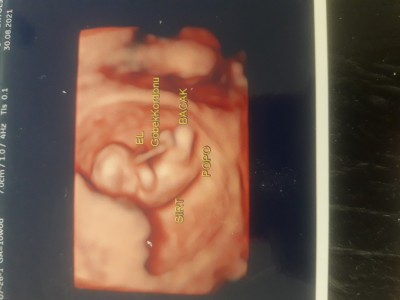

10+1 haftalik olduk bugun kontrolden geldik kalbimiz 180 atiyor dedi 2 hafta sonra yuzde 80 cinsiyeti soylerim dedi tecrubeli anneler tahmin yurutebilirmi once saglikli olsun tabi temennimiz o :)

11.hafta itibariyle cinsiyet oluşumu basliyor diye biliyorum bebegin cok küçük Allah bağışlasın.